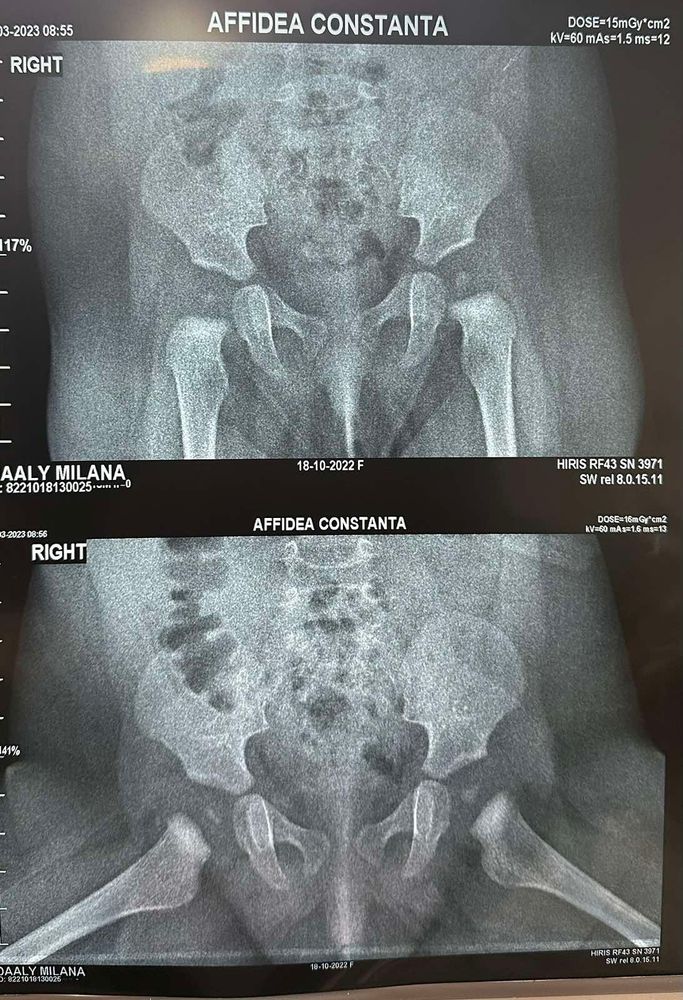

вот снимок , может кто то разбирается .

Валерия , вы даже сами посмотрите видно что они разные размеров и маленькие очень

Kuznetsova, нам сказали что ядра взлом возрасте формируются , к перекос это снимок так сделали нам (

Валерия , я не буду спорить. Но скажу, что в 2 мес у нас ядра были поболее ваших. На счёт косого снимка - это рукожопые специалисты 😬, теперь остаётся только гадать. Я б все заново перепроверила.

Валерия , как это рано? Электрофорез с кальцием наращивает ядра, которых у вас практически нет ☹️. Мы с 2х месяцев все делали. Массаж 40 мин и сразу после электрофорез по 1 минуте (вроде, или 2 не - помню уже) на каждую сторону. И все это курсами, выше писала. Вам нужно найти хорошого массажиста. И ортопед который ещё раз посмотрит снимок. Удивляет, что вам в описании не написали градусы смещения. А они есть, вы можете даже линейку положить и видно, что справа выше кость идёт. Ножки на длину ребёнка сравнивали, смотрели?

Kuznetsova, да по длине ножки измеряла все хорошо . Дело в том если посмотреть хорошо на снимок видно что ребенок лежит не ровно. Мы консультировались онлайн она измеряла но не сказала какие замеры . Сказала все в пределах нормы только ее смущают ядро . И посоветовала пить кальций витамин д и носить штаны .

По снимкам тут ничего не скажешь, в идеале к снимкам прикладывают специальную штуку с градусами и смотрят насколько отхождение от нормы.